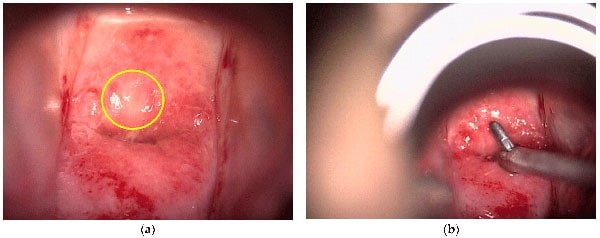

سپس یک محلول اسیدی ملایم با یک سواب پنبه ایی یا توپ پنبه ایی روی دهانه رحم و واژن شما مالیده می شود. این مایع باعث می شود که نواحی غیر طبیعی راحت تر دیده شوند. ممکن است احساس حین استفاده از این محلول احساس سوزش خفیفی داشته باشید.

چه زمانی در کولپوسکوپی بیوپسی انجام می شود؟

در طول کولپوسکوپی، در صورتیکه پزشک زنان شما نواحی غیر طبیعی را ببیند برداشتن بیوپسی از این نواحی انجام می شود. در طول بیوپسی، یک قطعه کوچک از بافت دهانه رحم، واژن یا فرج برداشته می شود و این نمونه جهت بررسی به آزمایشگاه پاتولوژی ارسال می شود. در حین انجام این کار یعنی برداشتن بیوپسی ممکن است احساس سوزش یا درد داشته باشید.